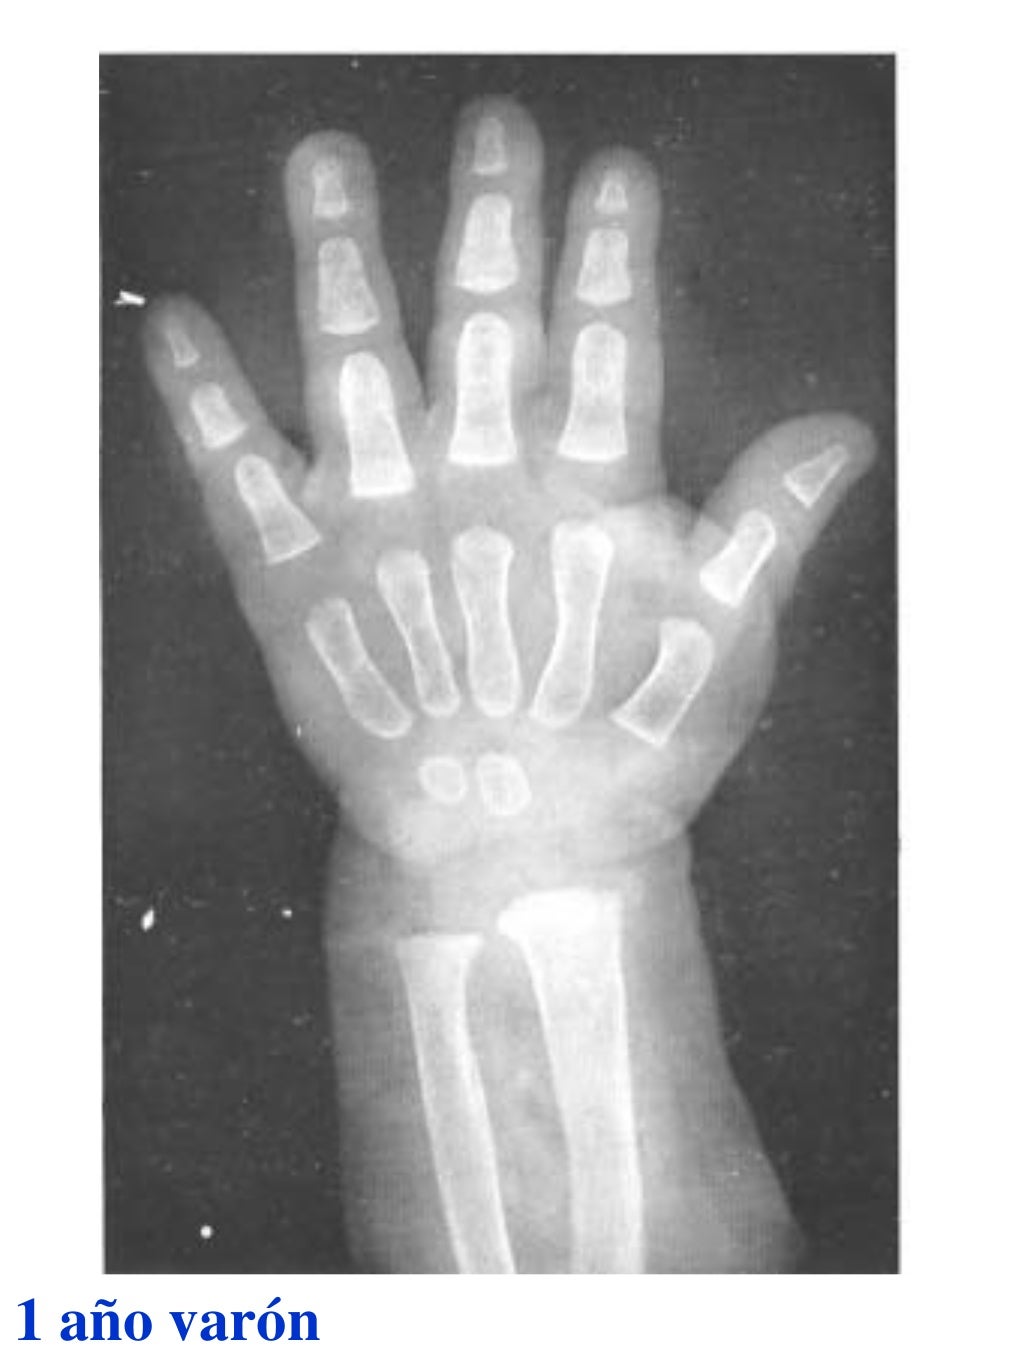

Tablas De Greulich Y Pyle . Scribd is the world's largest social reading and publishing site. This systematic review summarizes the. The radiographic atlas of skeletal development of the hand and wrist by ww greulich and si pyle is a classic radiological. The standards established by greulich and pyle, undoubtedly the most popular method, consist of two series of standard plates. The greulich and pyle method is one of the two main ways to assess the bone age of children. El documento lista las edades. Both main methods of bone age. 153 recomendaciones • 616,869 vistas. Atlas greulich y pyle | pdf | descarga gratuita. The greulich and pyle atlas is used to estimate the age of children and adolescents.

Tablas De Greulich Y Pyle The standards established by greulich and pyle, undoubtedly the most popular method, consist of two series of standard plates. The standards established by greulich and pyle, undoubtedly the most popular method, consist of two series of standard plates. El documento lista las edades. This systematic review summarizes the. The greulich and pyle method is one of the two main ways to assess the bone age of children. Both main methods of bone age. Scribd is the world's largest social reading and publishing site. 153 recomendaciones • 616,869 vistas. Atlas greulich y pyle | pdf | descarga gratuita. The greulich and pyle atlas is used to estimate the age of children and adolescents. The radiographic atlas of skeletal development of the hand and wrist by ww greulich and si pyle is a classic radiological.